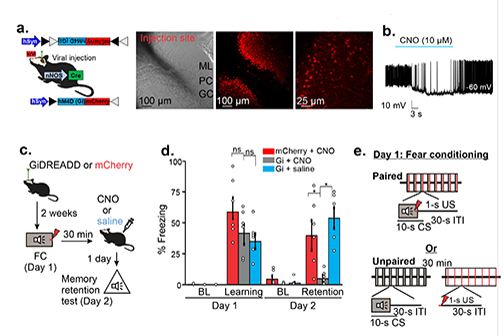

LSU Health New Orleans Study Identifies a Potential New Approach to PTSD Treatment

An LSU Health New Orleans research study led by Siqiong June Liu, PhD, Professor of Cell Biology and Anatomy, has found that cerebellar inhibitory interneurons are essential for fear memory, a type of emotional memory formation. Inhibitory interneurons within the cerebellar circuitry act as gatekeepers and control the output of the cerebellar cortex. The formation of fear memory requires the activity of these interneurons. The findings, which may lead to a novel treatment approach for post-traumatic stress disorder, are published in Cell Reports. More